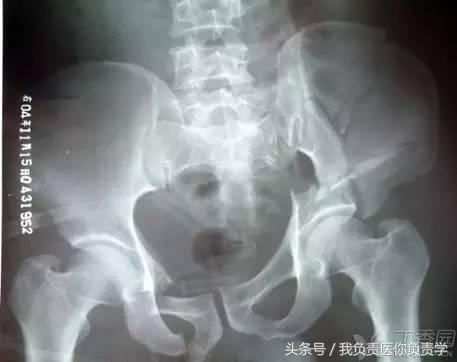

骨盆基本划线

a. Calve 线(卡尔维氏线):髂骨外缘与股骨颈外缘所连成的弧线,能反应股骨头与髋臼的关系及髋臼上缘的完整性。

b. 臼顶线 连接髋臼上缘的弧线,与泪滴外侧缘相续(黄线),代表髋臼的负重区。

c. Shenton 线(沈通氏线)耻骨下缘与股骨颈内侧缘所连成的弧线,正常时此线连续光滑,能反应股骨头与髋臼的关系。

d. 髂坐线 连接髂骨内缘与坐骨内缘的曲线,正常时此线为连续光滑曲线,能反应四边体的完整性。

e. 髂骶线 连接髂骨弓状线与骶骨岬的弧线,代表骨盆后环完整性。

f. 髂耻线 连接双侧髂骨内缘与耻骨上缘的弧线,代表骨盆前环的完整性。

g. 泪滴线(U形线)连接泪滴周围所形成的曲线,代表髋臼的内缘,一般用于髋臼假体深度的评价,髋臼内缘紧邻泪滴线的外缘。

h. 前唇线 髋臼前缘所连成的弧线,代表髋臼前壁的完整性。

j. 后唇线 髂骨外缘与髋臼后缘所连成的弧线,代表髋臼后壁的完整性。

k. 闭孔内缘线 沿闭孔内缘所连成的弧线,正常情况下双侧闭孔对称,当骨盆旋转时可发生改变。